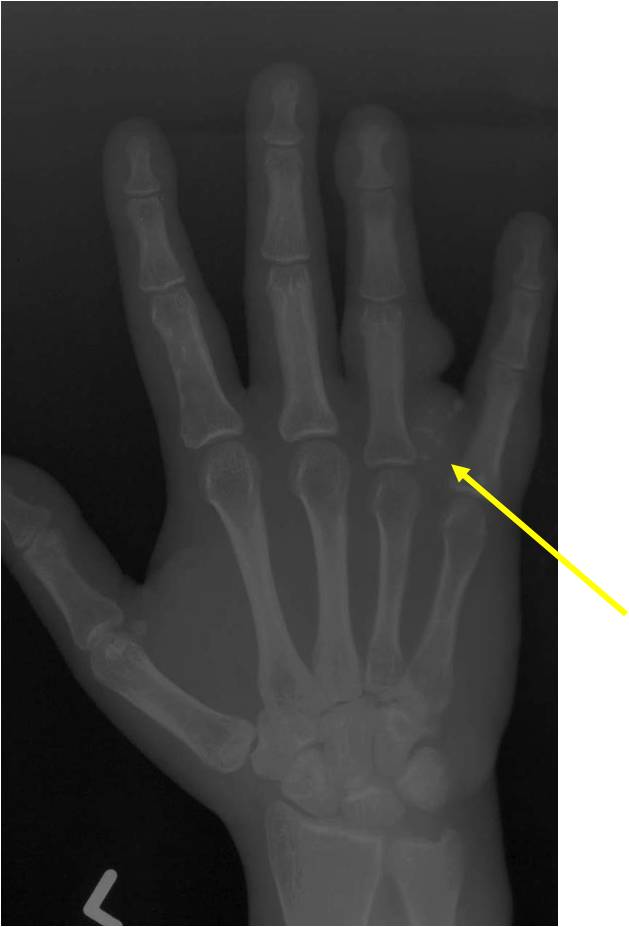

- 50% involve hands and feet (mostly phalanges)

- Localized, radiolucent defect usually with punctate calcifications

- Calcifications are stippled, punctate, popcorn like calcifications and “Ring and Arc” calcifications

- Cortex may be scalloped and thinned in the phalanges

- Geographic lytic lesion

- Expansile remodeling with thinned cortex

- Chondroid matrix with calcifications in majority of tumors

- Digits: Impending or actual pathological fracture

- Intralesional curettage and bone graft or cement